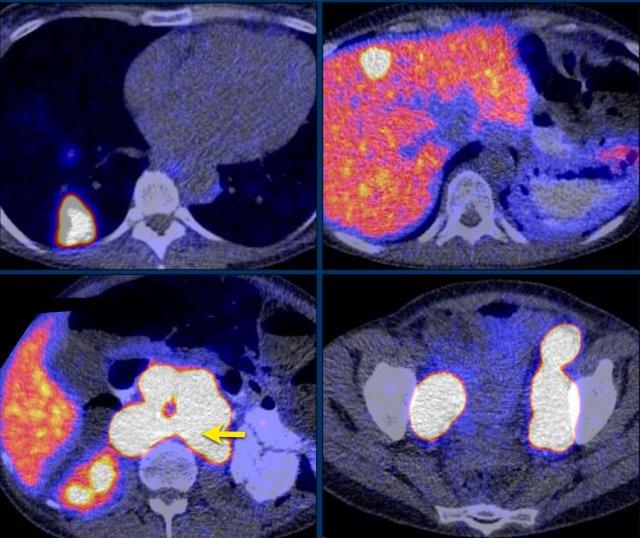

CT thì động mạch và thì tĩnh mạch mặt cắt ngang cho thấy một u tình cờ tuyến thượng thận trái tăng sinh mạch máu.

Metanephrine tự do trong huyết tương tăng cao, có giá trị chẩn đoán u tủy thượng thận (pheochromocytoma).

Phân giai đoạn tiếp theo bao gồm SPECT MIBG và PET-CT FDG, cả hai đều cho thấy sự hấp thu mạnh tại khối u tuyến thượng thận trái, nhưng không có bằng chứng bệnh di căn.